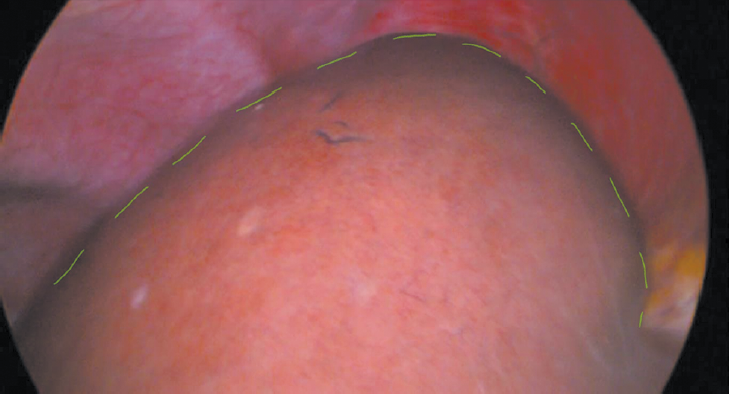

Под комбинированной анестезией параумбиликально, доступом по Хассену установлен лапаропорт. Карбоксиперитонеум — 12 мм рт. ст., установлены оптическая система, троакары с рабочими инструментами: 2 троакара по 5 мм — в правое подреберье, троакар 12 мм — в эпигастрии. При ревизии: прядь сальника и 12-перстной кишки подпаяна к краю правой доли печени (спайки разобщены). В брюшной полости выпота нет. Желчный пузырь размером 10 × 4 × 4 см. Раздельно выделены, клипированы и пересечены пузырный проток и пузырная артерия. Выполнена холецистэктомия «от шейки». Ложе желчного пузыря обработано электрокоагуляцией. В проекции VII сегмента с переходом на VIII сегмент печени визуализирована киста (рис. 2).

Рис. 2. Киста печени

Fig. 2. Liver cyst